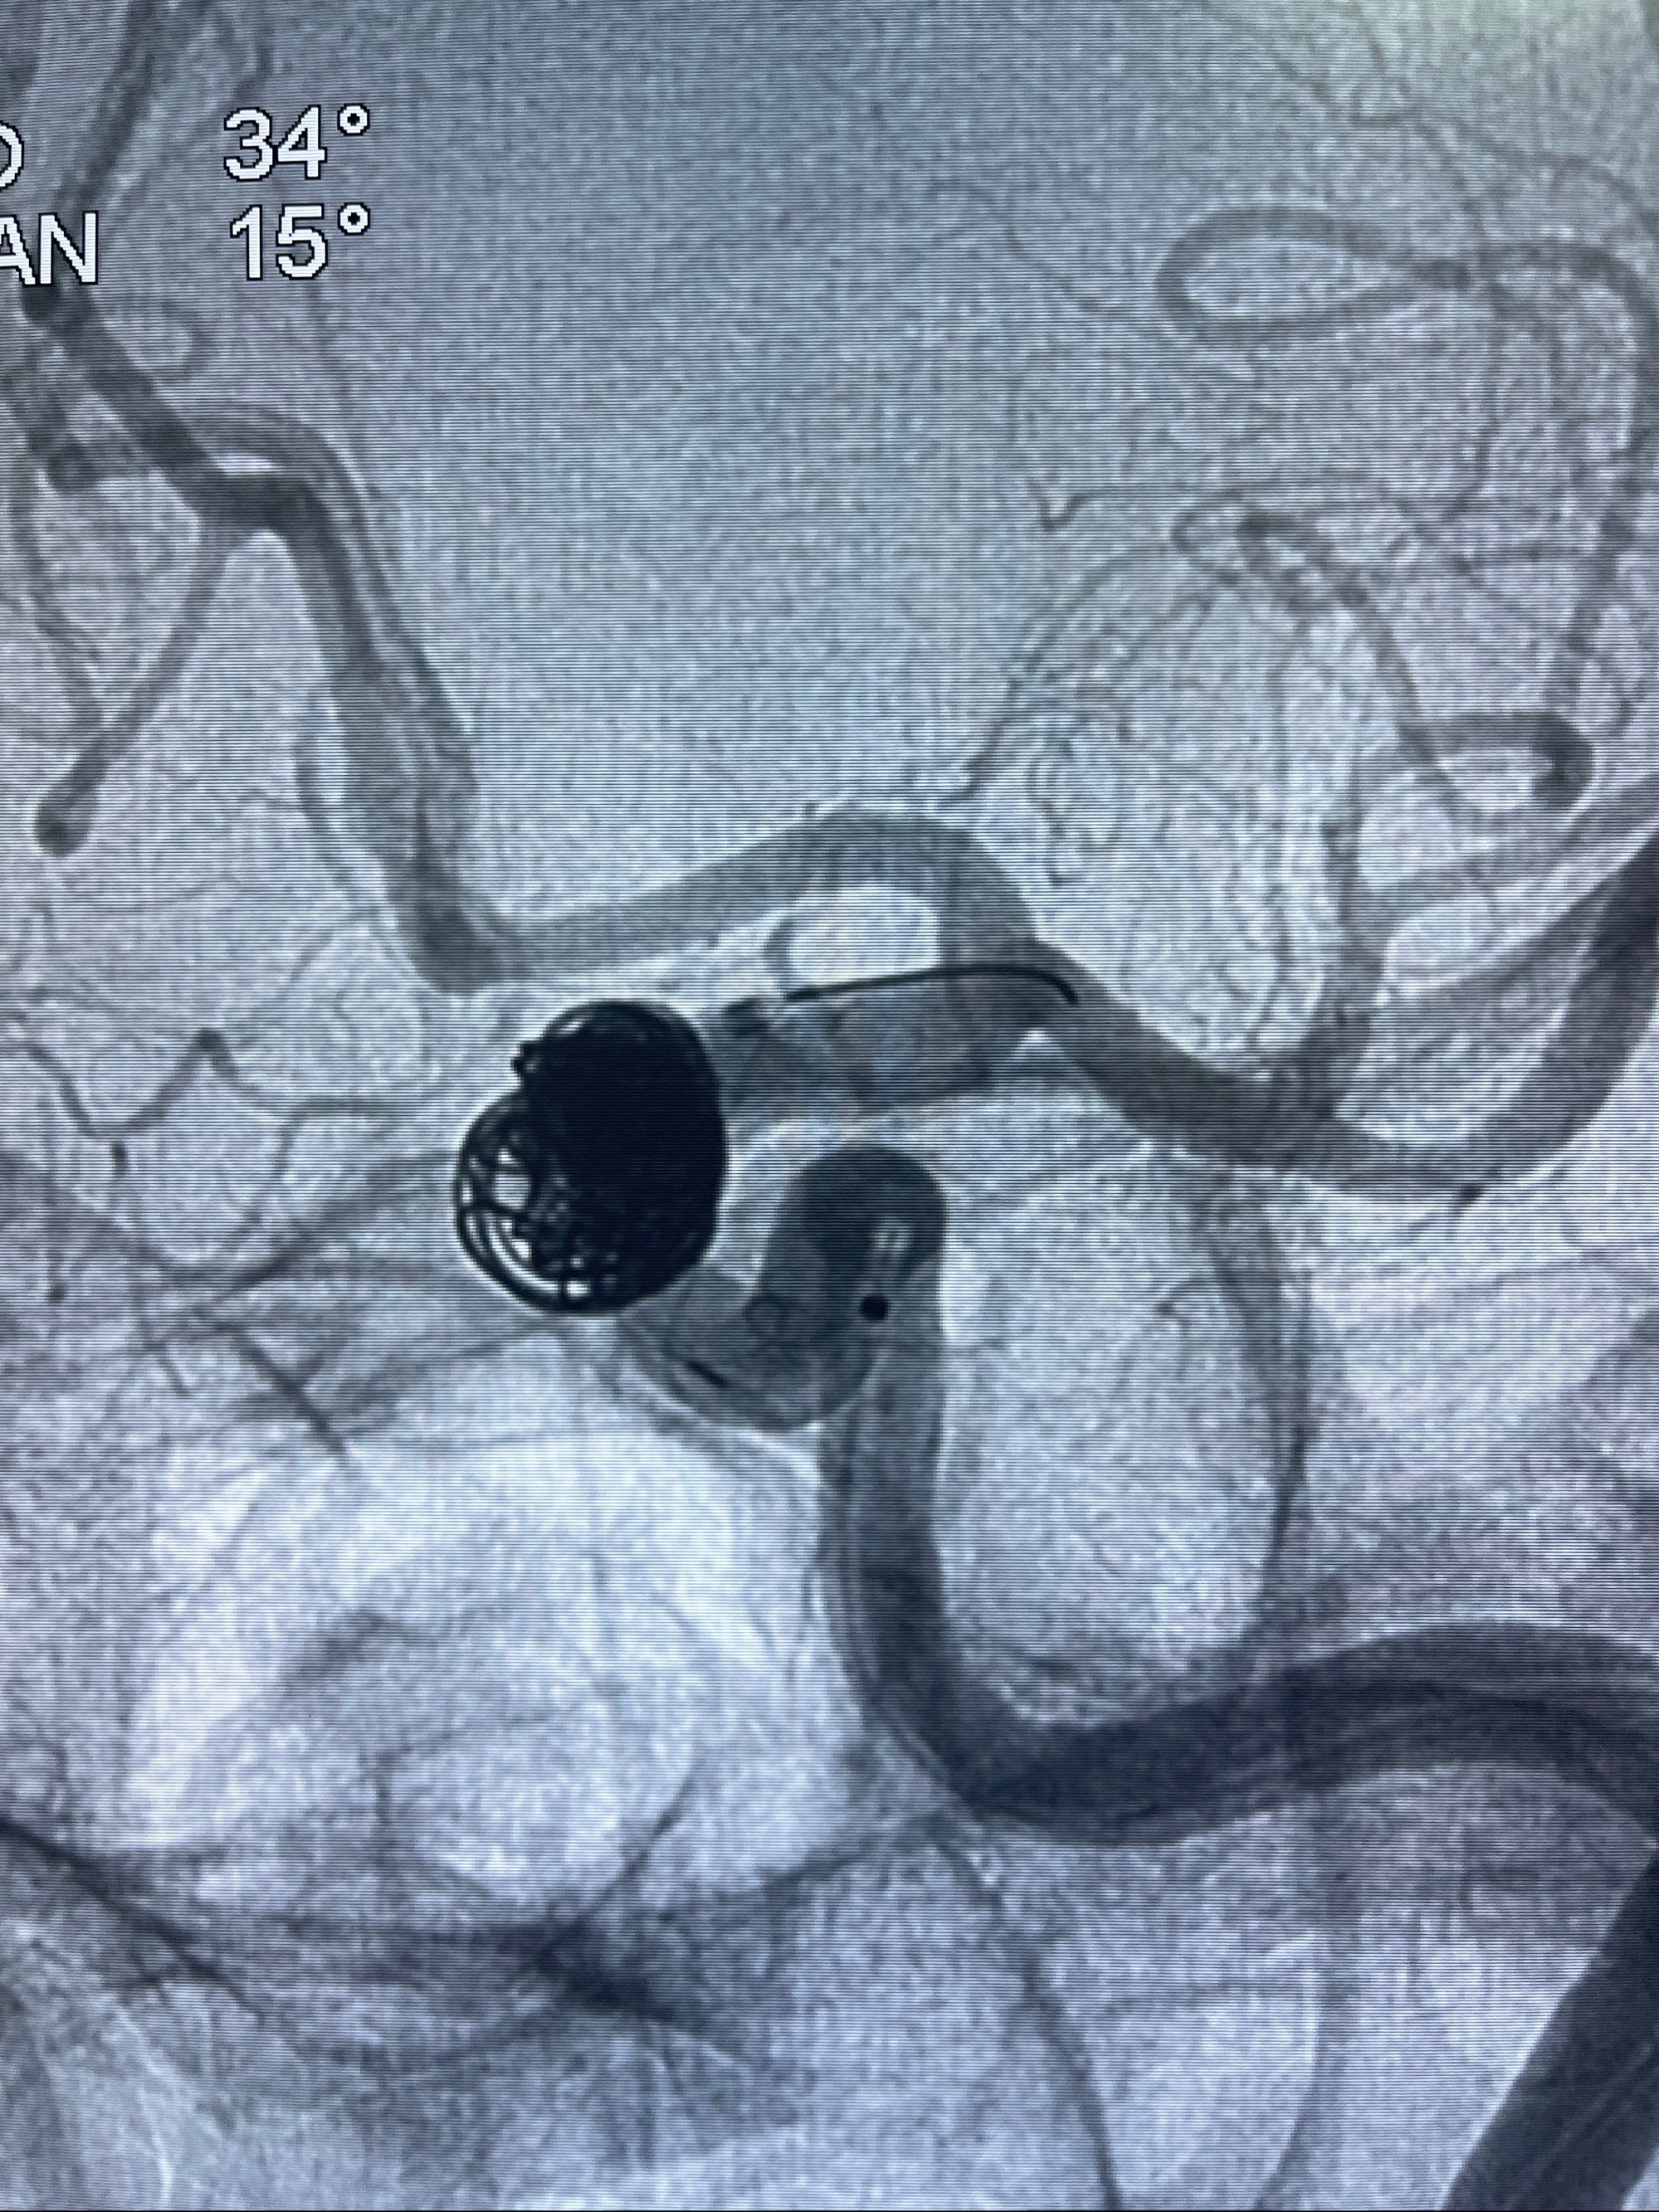

2023-08-30DSA:左侧颈内动脉眼动脉动脉瘤,约3*9.2*7.3mm大小

2023-09-06全麻下行左侧颈眼动脉瘤

密网支架辅助栓塞

- Tubridge 4.0-20mm密网支架

- 加奇微弹簧圈:7*30/6*20/5*20/2*8

术后3D显示支架贴壁佳

麻醉苏醒佳,遵嘱活动!视力视野正常。